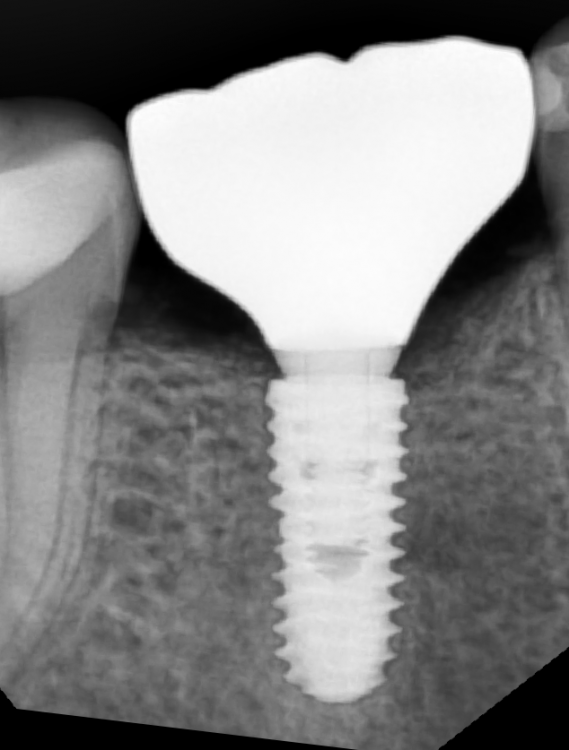

АнтонТЛТ Опубликовано 15 мая, 2023 Поделиться Опубликовано 15 мая, 2023 Сделайте прицельный внутриротовой рентген. Выглядит как будто неправильно изготовлена коронка Ссылка на комментарий

АнтонТЛТ Опубликовано 15 мая, 2023 Поделиться Опубликовано 15 мая, 2023 Если немного корректируют, то нормально. Если сильно по высоте снижают, то верхний зуб начнет выдвигаться. По этому снимку к имплантату нет вопросов. Правильно сделанный прицельный снимок снимет сразу несколько вопросов. И фотография коронки хорошего качества тоже не помешала бы Ссылка на комментарий

MariiaF Опубликовано 1 июня, 2023 Автор Поделиться Опубликовано 1 июня, 2023 Здравствуйте! Пришлось делать новый всё-таки снимок, ну и фото коронки без него не было смысла постить. https://hostingkartinok.com/show-image.php?id=cc02827df76c9979c8e2128519ca6cae https://hostingkartinok.com/show-image.php?id=bac696444a539cc3af276d4215e62264 прямо на сайт не выкладывается, опять Ссылка на комментарий

АнтонТЛТ Опубликовано 1 июня, 2023 Поделиться Опубликовано 1 июня, 2023 По рентгену складывается впечатление, что коронка как будто немного перекошена (это если прям выискивать к чему предраться). По фото видно, что десна немного воспалена. Анатомия бугров коронки выглядит очень выраженной, если сравнивать со стираемостью соседних зубов. Ссылка на комментарий